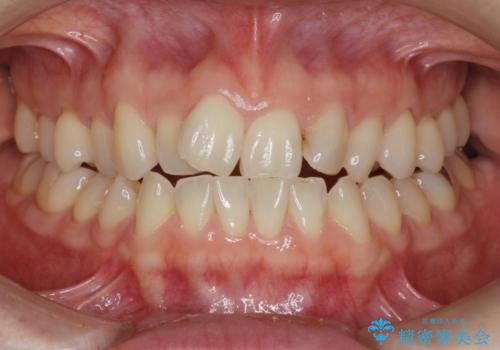

インビザラインで行う前歯のみの部分矯正

- 長年気になっていた前歯の歯並びを改善したいと、矯正治療を希望され思い切って来院されました。

費用と期間を相談し、「気になっているのは前歯だけ。」とのことでしたので前歯のがたつきのみをインビザラインで改善する矯正治療の計画を立てます。

しっかりとマウスピースの装用時間を守っていただき、非常にスムーズに治療を終了することができました。